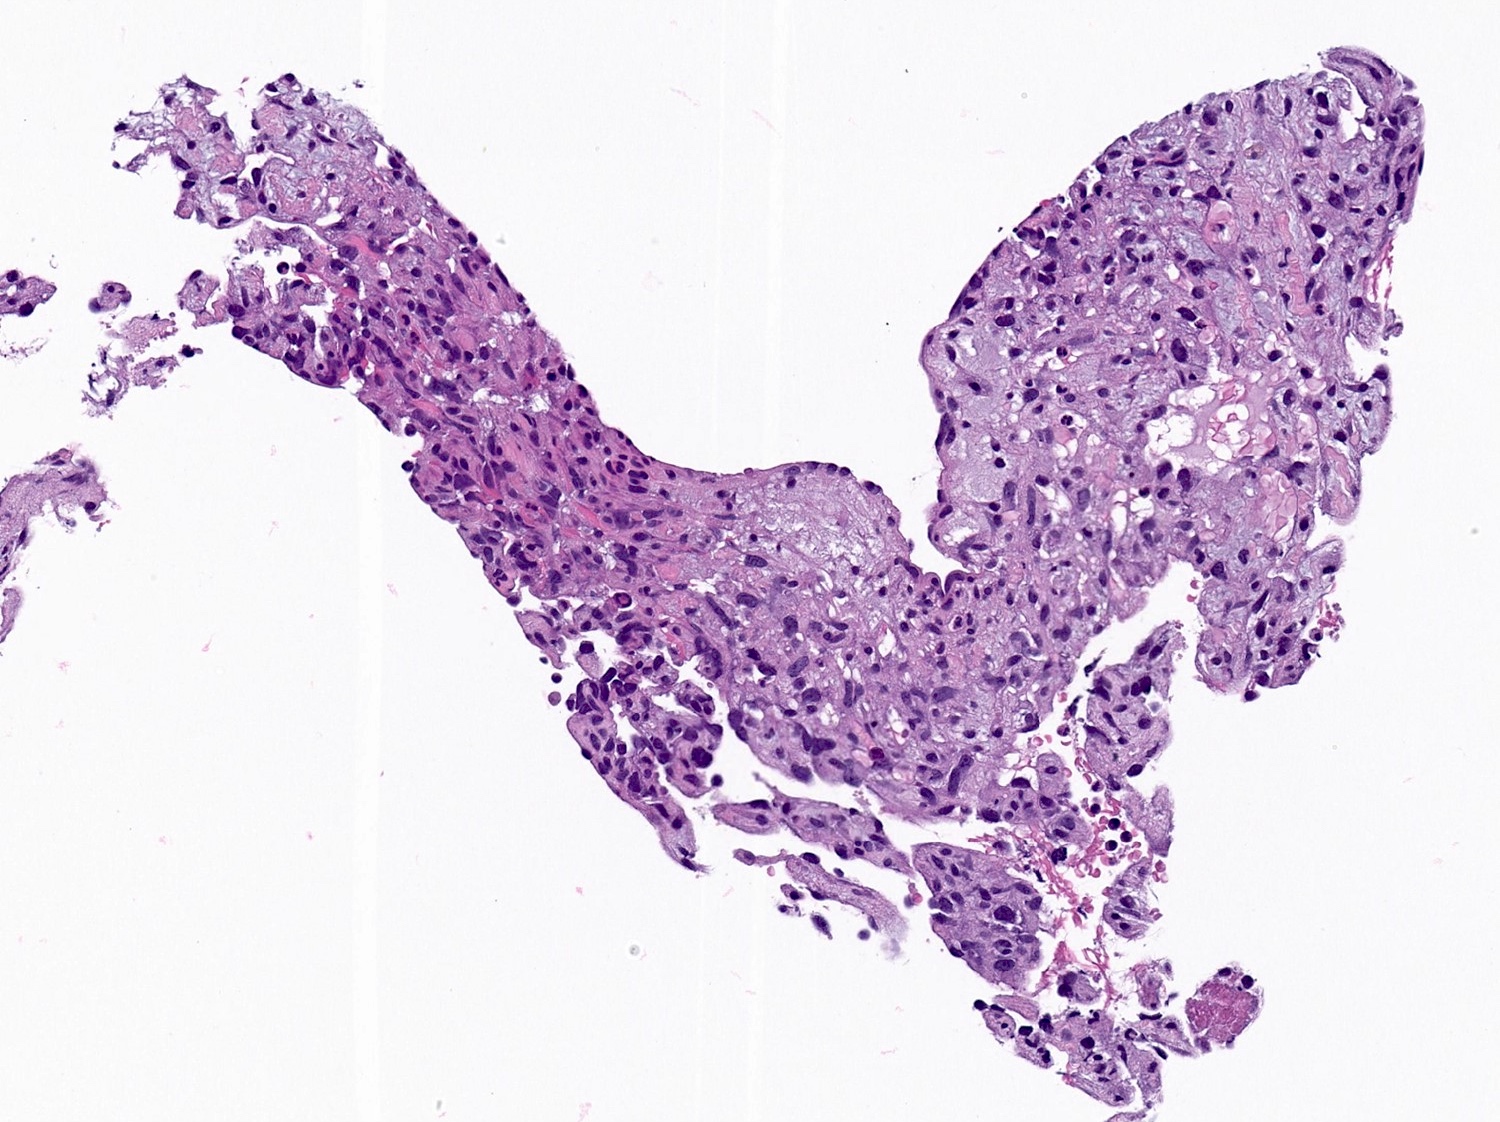

Microscopic (histologic) description

- 2 main histologic growth patterns were described (Am J Surg Pathol 2019;43:581)

- Non-mass forming

- Sinusoidal

- Dilated sinusoids lined by atypical endothelial cells seen in angiosarcoma with hyperchromatic nuclei

- Peliotic

- Blood pools and fibrin surrounded by hepatocytes

- Peripheral clusters of atypical endothelial cells seen in angiosarcoma mixed with inflammatory cells may extend into the sinusoids

- Mass forming

- Vasoformative shows architectural complexity and interconnecting vascular channels

- Anastomosing vessels and haphazard vascular channels

- Endothelial cells show tufting, atypia and mitotic figures

- Nonvasoformative shows epithelioid to spindled morphology

- Epithelioid morphology (epithelioid angiosarcoma) is most common (Am J Surg Pathol 2004;28:298)

- Solid nests or sheets of tumor cells

- Tumor often invades into sinusoids and hepatic venules at the periphery

- Cells have eosinophilic cytoplasm and oval nuclei

- Chromatin can be vesicular

- Multinucleated giant cells can be present